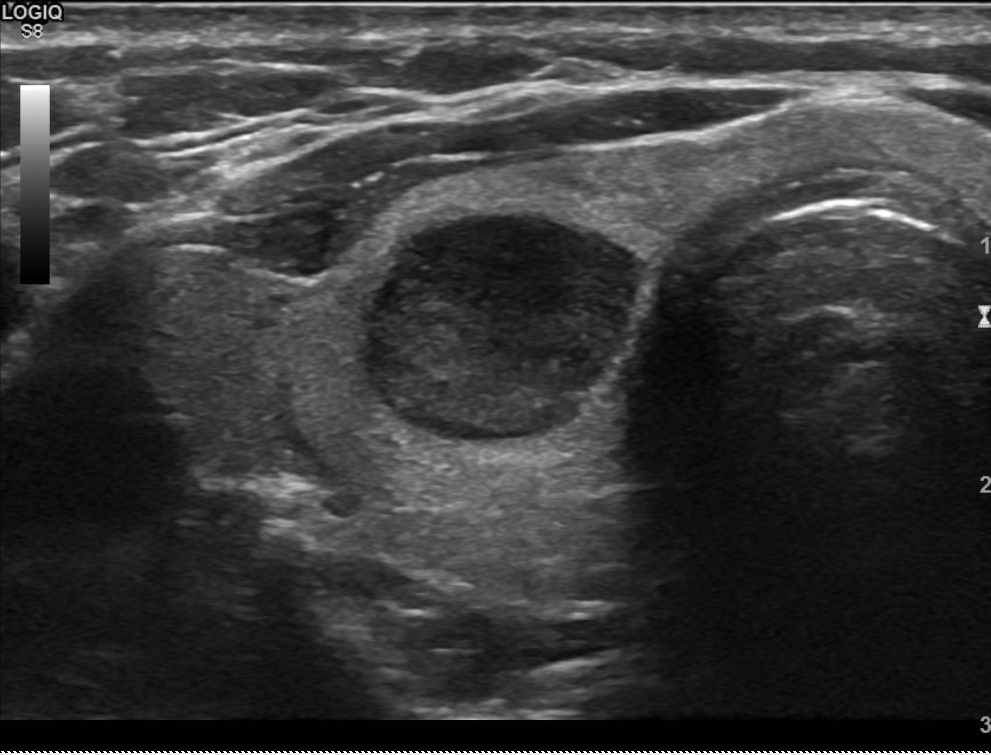

EU-TIRADS 3

Les nodules classés EU-TIRADS 3 sont tissulaires ou à prédominance tissulaire, isoéchogène par rapport au tissu thyroïdien péri-nodulaire et bien limités avec une capsule périphérique souvent bien visible. Il s’agit des nodules les plus fréquents.